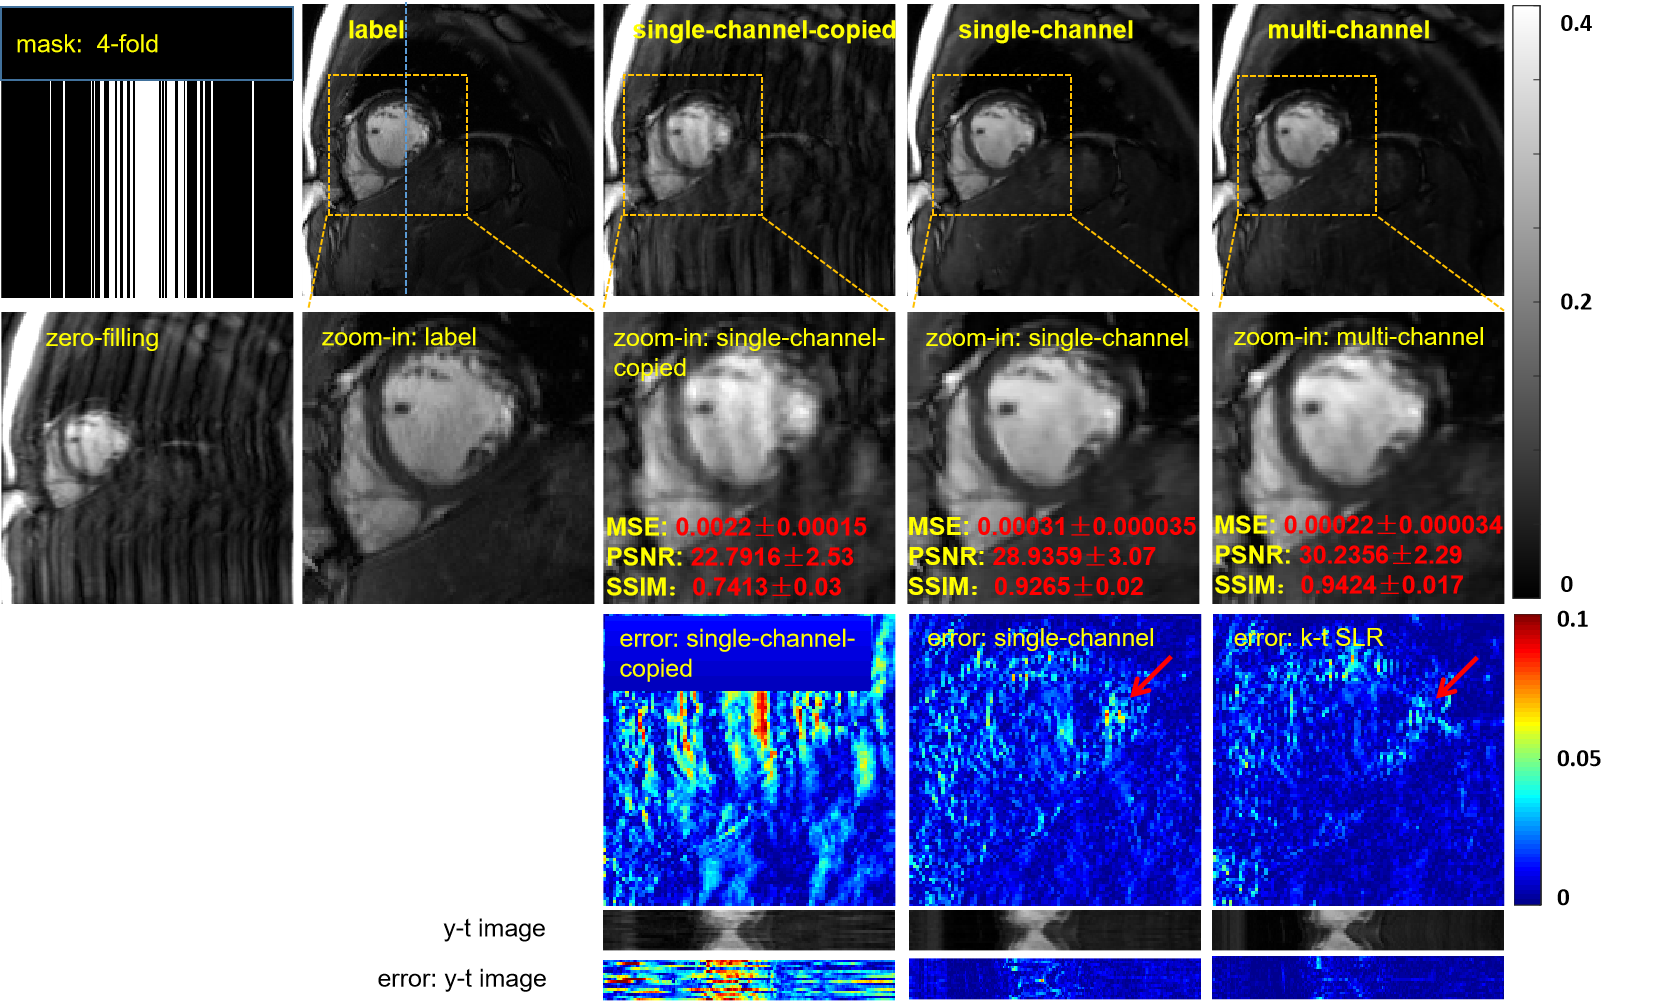

Currently, all three deep learning methods [22, 23, 24] for cardiac MRI use single-channel data for network training and testing. In this section, we refer to these methods as single-channel methods and correspondingly refer to the proposed parallel imaging method as the multichannel method. We will explore whether the multichannel method exhibits superior reconstruction performance. To ensure a fair comparison, we explored the effectiveness of the single-channel methods and the multichannel method based on the same network structure (ADMM-Net-III) under the unsupervised framework proposed in this paper. Although we show only the unsupervised scheme in the multichannel case in Fig.1, this unsupervised scheme can be conveniently changed to a single-channel case because the operations in Fig.1 focus on the temporal dimension and have nothing to do with the coil dimension. The two models differ in only two respects. First, the raw materials for data preparation are different: one consists of multichannel fully sampled k-space data, while the other consists of single-channel fully sampled k-space data by adaptively combining the above multichannel k-space data [43]. Second, the single-channel model does not require a network to combine the coils; therefore it includes only the reconstruction part. In addition, to prove that the superiority of the multichannel model over the single-channel model is due to the ability of the multichannel model to learn the correlations between the coils rather than the model’s capacity, we built a new single-channel model with the same network structure as the multichannel model we proposed, but for which the input data are multiple copies of the single-channel data. We call this model the single-channel-copied model.

We trained these three models with a 1D random Gaussian sampling mask at 4-fold acceleration. The reconstruction results of the three models in Fig.7 clearly shows that the multichannel model restores more details (as indicated by red arrows) than does our single-channel model. The single-channel model not only loses more detail than the multichannel model, but also the reconstruction results are blurrier. The single-channel-copied model failed to reconstruct the dynamic MR image, despite having the same network structure as the multichannel model. Therefore, we can conclude that the proposed multichannel model achieves good reconstruction results because it explores the coil correlation well. The reasons why the dynamic MR image cannot be reconstructed as well in the single-channel-copied model may be as follows: (1) Each coil network learns the same features, resulting in an overspecificity of features, which reduces model generalizability; and (2) the errors or noise in each feature from each coil network have a superposition effect, resulting in large reconstruction errors.